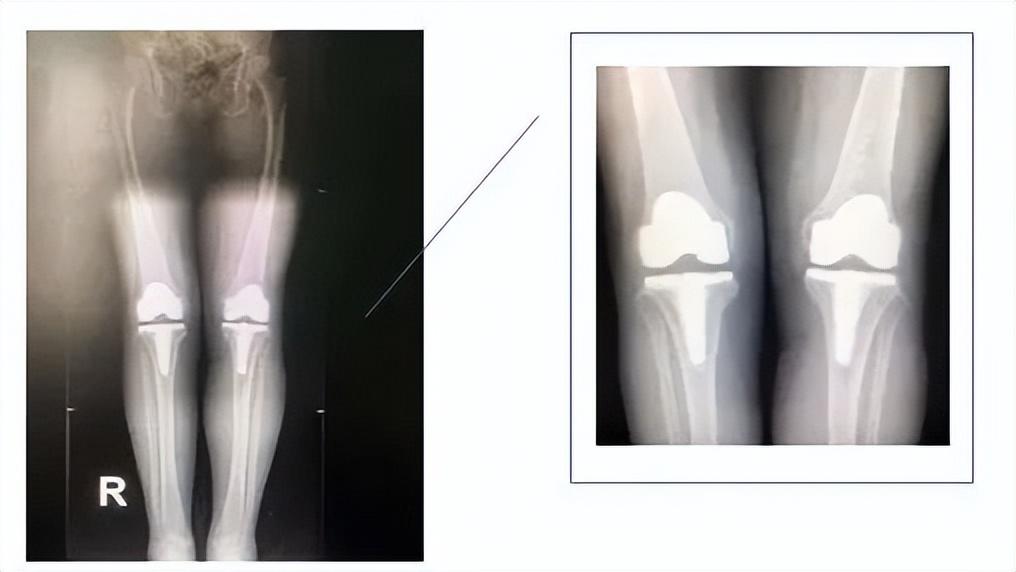

术前拍片示双膝内翻畸形、骨质增生

术后拍片示双膝关节立线纠正,内外间隙平衡